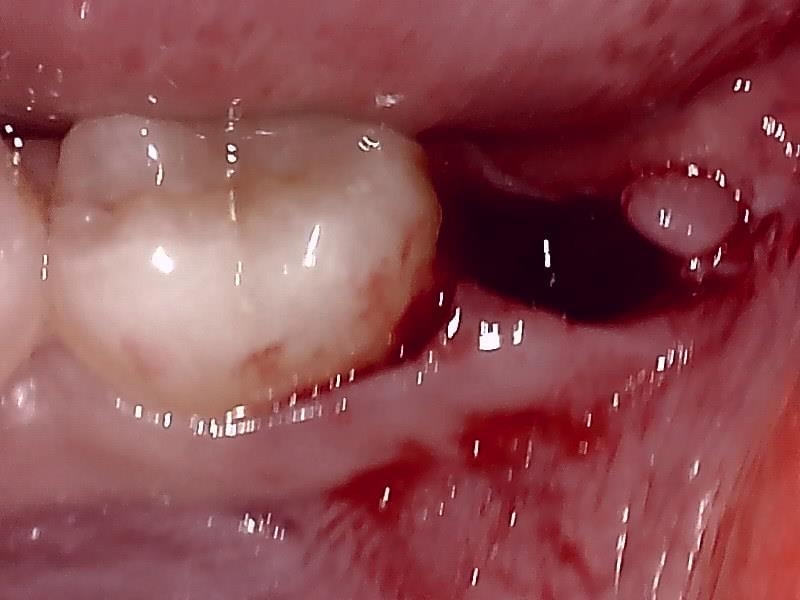

左下の抜歯窩

左下の縫合

当院では、傷口は最小限に、骨は極力削らずに行います。

骨が歯を覆っているケース以外は骨を削ることはありません。

親知らずのみにアプローチし歯を分割し最小限の傷口で取り出します。

歯肉を切開し、歯が見えるようにして、

周辺の骨を削らないように親知らずを分割し抜きやすくしていきます。

この抜歯法により術後の腫れ痛みが大幅に軽減されます。